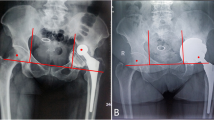

We included three (15.8%) Paprosky type IIC, 11 (57.9%) type IIIA, and 5 (26.3%) type IIIB hips, according to acetabular Paprosky classification [4]. A pelvic discontinuity was identified in one patient (Figs. 2 and 3). A modular technique was adopted in three patients. The mean number of screws used for primary acetabular component fixation was 2.1 ± 1.8.

Radiographic analysis showed no evidence of custom device loosening or migration. All custom-made implants appeared well osseointegrated. In two (10%) hips, incomplete and not progressive < 2 mm radiolucent lines were observed. The average inclination of the shell was 48 ± 9.5°, excluding one patient with contralateral previous Girdlestone procedure. The mean post-operative LLD was 4.6 ± 3.9 mm. No case of stem subsidence was reported. The radiographic evaluation within the first post-operative year showed two cases of heterotopic ossification Brooker Grades I and II. These did not require surgical re-operation, had good clinical results, and displayed no progression on subsequent radiographs. For radiological parameters, very good (≥ 90%) Cohen’s kappa inter-rater agreement was found.

The underlying philosophy is to produce a custom acetabular implant that maximises the implant-bone interface. This feature combined with the high grip strength of porous titanium ensures a primary press-fit stability bypassing the need of flange and screws. Accurate pre-operative planning, the preoperative trial surgery, and meticulous planning of safe screw insertion zones to avoid injuries to the neurovascular structures are the key points of custom-made acetabular implants. Ideally, these advantages lead to a shorter operative time and limit blood loss especially in the case of multidirectional bone defects [18]. Accurate pre-operative planning of screw direction improves primary implant stability and is of paramount importance in case of pelvic discontinuity in order to restore the continuity of innominate bone.